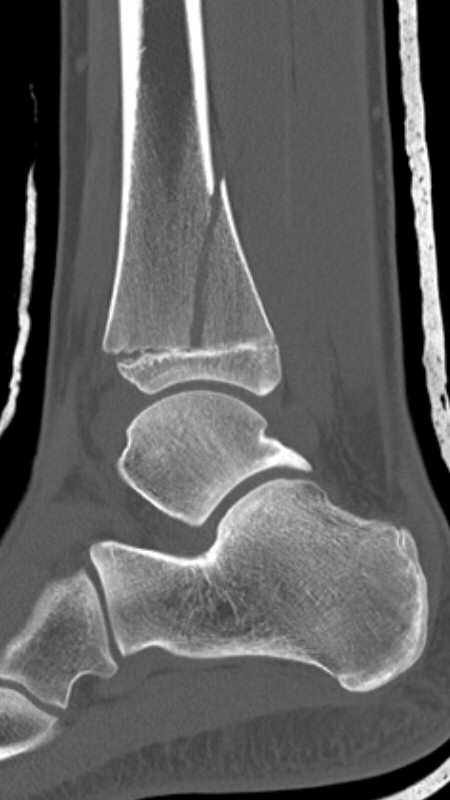

Distal tibiafyseolys SH 3 Tillaux (barn)

Salter-Harrisfraktur typ III, med avulsionsfraktur av anteriora/inferiora tibiofibulära ligamentet, motsvarar syndesmosruptur hos vuxna.

Gör DT för att avgöra felställning vilket avgör behandlingen.

Distal tibiafyseolys SH 4 triplansfraktur (barn)

Triplanfraktur = triplansfraktur = treplansfraktur: fraktur i distala tibia som engagerar både metafys, fys och epifys. Kan vara 2, 3 eller 4 fragment. I 50 % av fallen är även fibula frakturerad [3].

Exempel på triplansfraktur hos nästan färdigvuxet barn

På akutmottagning

Gör DT för att avgöra frakturtyp och felställning.